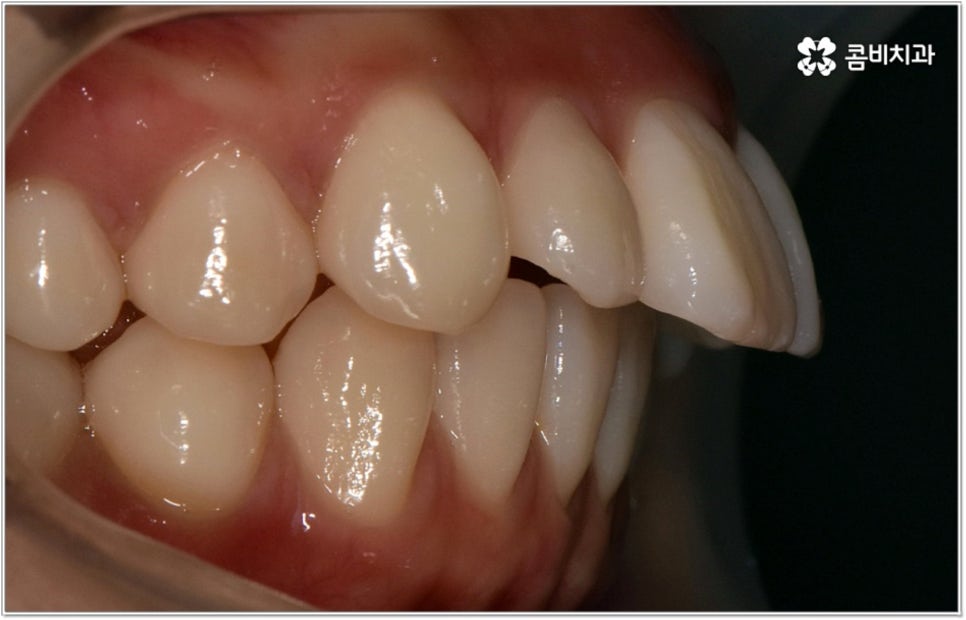

위아래 치열이 제대로 맞지 않으면 식사를 할 때 불편하고 발음이 샐 수 있습니다. 부정교합의 정도가 심하지 않아서 이러한 기능적인 문제가 당장은 크지 않다고 하더라도 성장을 하면서 잘못된 교합에 적응하고 악화되는 쪽으로 악관절이 발달한다면 불편함이 커지는 것은 물론 씹을 때 통증이 생기거나 안면비대칭 현상까지 초래할 수 있기 때문에 어릴 때부터 주의하는 것이 좋습니다

이러한 기능적인 부분 외에 심미적인 부분에서도 문제가 발생할 수 있는데요. 예를 들어 치아가 튀어나와 있다면 가만히 있어도 퉁명스러워 보이거나 화가 난 것처럼 느껴지고 입을 꼭 다물기가 어려워서 무리하게 힘을 주게 되기 때문에 입가나 턱에 주름이 질 수도 있어요. 이때 돌출입치아교정 치료를 받게 되면 위아래가 잘 맞물리는 가지런한 치열을 가지게 되는 것 뿐 아니라 자연스러운 입매와 부드럽고 균형잡힌 인상으로 바뀌게 되어 스스로 자신감 있는 태도를 가지게 되고 대인 관계에서 호감도도 높아질 거예요.